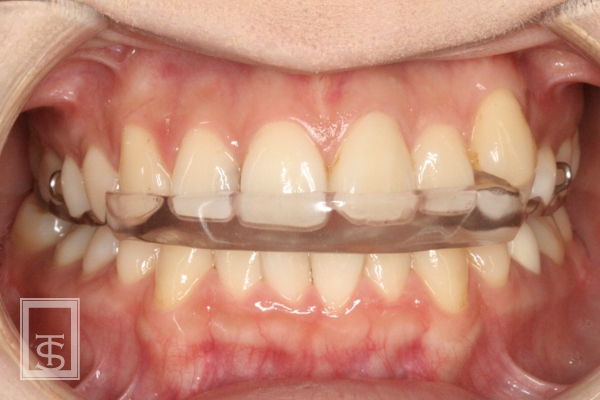

スプリント療法(Splint therapy)

顎関節症治療に用いられている方法で、マウスピース型の装置を口腔内にはめて、顎関節症の原因となっている口腔習癖や左右の顎のアンバランスを改善する治療法となります。

顎関節症状の有る場合、潜在的に顎関節のリスクが高い場合、顎位の不安定な場合などに症状の改善、顎関節のリスク評価、顎位の確認などに行います。

通常は上顎にマウスピース状の装置を使用します。

使用期間は症状や使用状況により異なります。